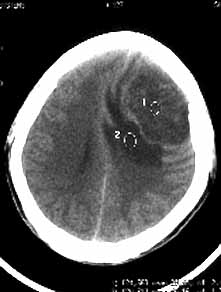

男性,36岁,头痛数年,近期伴有视蒙。

ct诊断:左额颞部脑膜瘤。